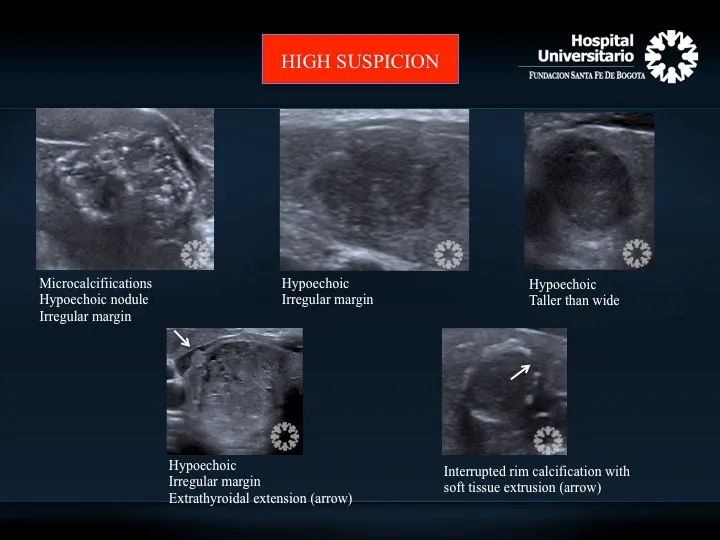

- USG: Initial. Suspicious: microcalcifications, hypoechogenicity, irregular margins, taller-than-wide, ↑vascularity.